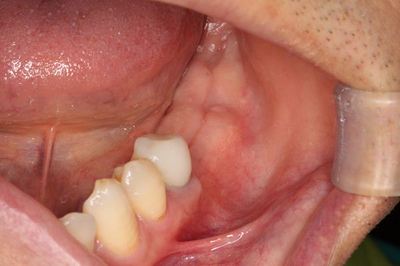

縫合を終えました。

オペ終了時のレントゲン写真です。

O・Kさん、オペおつかれさまでした。